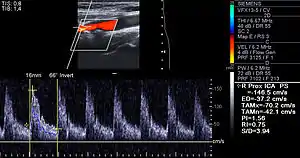

Doppler ultrasound of right internal carotid artery with calcified and non-calcified plaques showing less than 70% stenosis

Lumen stenosis that is greater than 75% was considered the hallmark of clinically significant disease in the past because recurring episodes of angina and abnormalities in stress tests are only detectable at that particular severity of stenosis. However, clinical trials have shown that only about 14% of clinically debilitating events occur at sites with more than 75% stenosis. The majority of cardiovascular events that involve sudden rupture of the atheroma plaque do not display any evident narrowing of the lumen. Thus, greater attention has been focused on "vulnerable plaque" from the late 1990s onwards.[80]